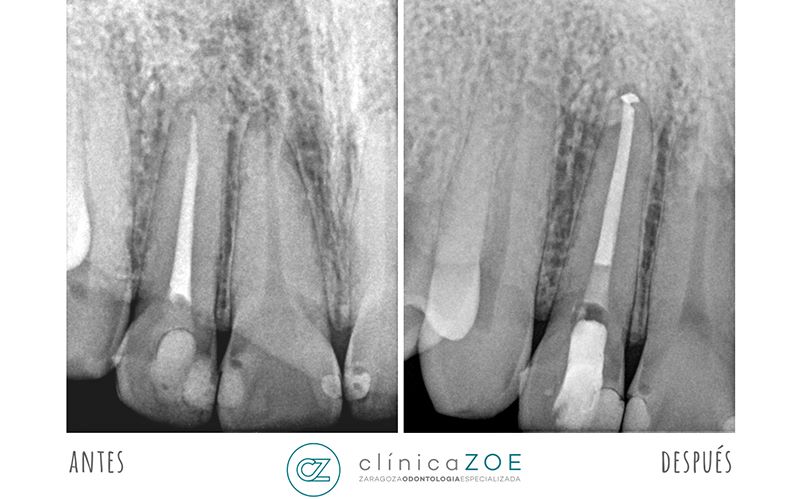

Cuando nos encontramos ante una endodoncia fracasada o realizada de forma incorrecta, la primera opción de tratamiento siempre debe ser tratar de mejorarlo. En la mayoría de las ocasiones, tras un correcto análisis de las causas que han producido el problema, se puede mejorar la situación inicial y el paciente puede mantener su diente y comer con normalidad. Para ello, en Clínica ZOE – Zaragoza Odontología Especializada siempre realizamos una radiografía tridimensional (TAC dental) previa que nos permitirá poder enfocar el caso de manera adecuada.

La reendodoncia suele ser un tratamiento de dificultad elevada, que requiere de un profesional cualificado y con la experiencia suficiente para poder llevarlo a cabo con éxito. Además, el uso del microscopio dental es de especial importancia en este tipo de tratamientos. Con él nos aseguramos de poder retirar todo el material previo, desinfectar el interior del diente y volver a rellenarlo adecuadamente de nuevo.